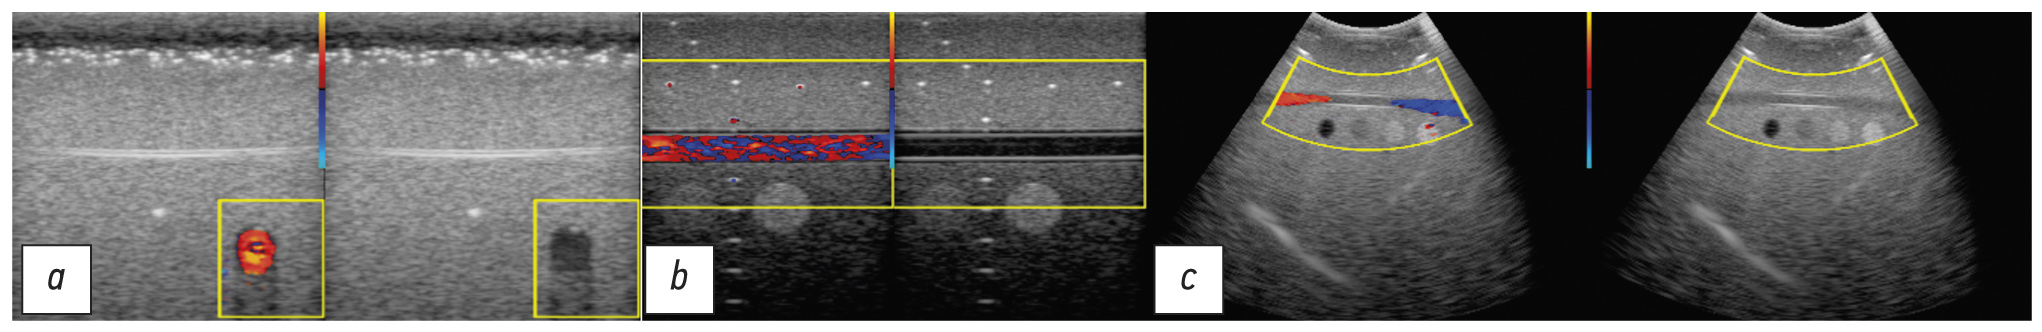

Fig. 6 shows the external view and scheme of the phantom, and Fig. 7 shows examples of sonograms. In transverse scanning, the linear transducer was positioned at an angle of 60° to the vessel, the flow rate was 30 cm/s, data were obtained at 5, 9, and 17 pulses in train, and the pulse repetition frequency was 2.5 kHz. Concurrently, an observed sonogram in the phantom was very much alike that of the in vivo carotid artery.

In the course of longitudinal scanning with a linear transducer, the flow velocity was set to 50 cm/s, and the study was conducted with 17 probing pulses and a frequency of 1 kHz. The velocity projection, which was displayed in the Doppler mode, was close to zero. Such a study may be useful for debugging mapping algorithms.

Longitudinal scanning with a convex transducer was also performed, while three examinations were conducted at different flow rates (i.e., 30 cm/s, 65 cm/s, and 100 cm/s) at a pulse repetition frequency of 2 kHz. For these examinations, a convex transducer was used. The estimated value of the flow velocity projection along a horizontal vessel varied from a negative value, passing through zero, to a positive value; the vessel was colored in the whole palette of the CFM mode.

Fig. 7. Sonograms of the Gammex phantom: a - when examining with a linear transducer at an angle of 60º to the flow; b - parallel to the flow; c - when examining with a convex probe.

In Fig. 7 and all subsequent sonograms, both the B-image with the superimposed CFM imaging and the B-image without CFM are placed side by side. Subsequent examinations were conducted using a linear transducer, since it is commonly used in small depth examinations. Preference was given to small values of the pulse repetition frequency since both types of twinkling artifact signals be registered in this case [32].